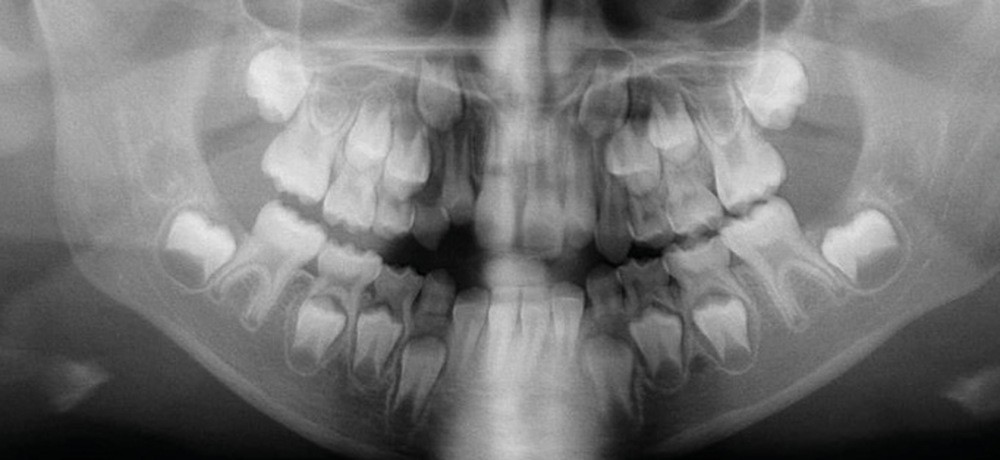

Cette patiente a été suivie dans le cadre d’un traitement interceptif alors qu’elle avait 9 ans. Elle présentait une endognathie maxillaire et une béance antérieure importante liées à des troubles fonctionnels évidents. En effet, l’examen clinique révélait une ventilation buccale exclusive, des ronflements nocturnes et une déglutition atypique. Nous avions noté à l’époque un manque de place pour l’évolution des dents définitives et un inversé d’articulé bilatéral. Les parents avaient rencontré un médecin ORL, mais avaient refusé une intervention visant à enlever les amygdales. Les deux canines maxillaires étaient incluses (fig. 1 à 6).

Quelques années plus tard, au moment de démarrer sa prise en charge orthodontique, la patiente présentait à nouveau une béance antérieure, un décalage des milieux incisifs de 2 mm et le problème transversal avait récidivé. Lors de l’examen clinique, elle présentait un inversé d’occlusion bilatéral postérieur et une ventilation buccale exclusive. À la suite du refus de réaliser l’amygdalectomie de façon précoce, elle ronflait toujours et sa déglutition ne s’était pas modifiée malgré des séances d’orthophonie (fig. 7 à 15).